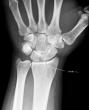

She was walking to work and fell in a pothole. Corey, who do we go after for this? So now we're in the ER, waiting for X-ray results or maybe some pain meds. At least we're not in Nepal. Or Baltimore. Acts of injustice done between the setting and the rising sun in history lie like bones, each one. -W H Auden

It was her wrist, not her leg, but they think no fracture...they'll know in a week when the swelling subsides.

My sweetheart wasn't on her phone and was very alert but those damn potholes sneak up on you...